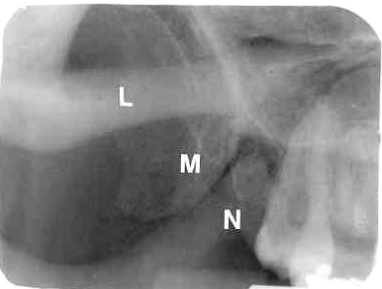

23. What is showing by A?

24. What is showing by N?

25. What is shown by M?

26. What is shown by L?